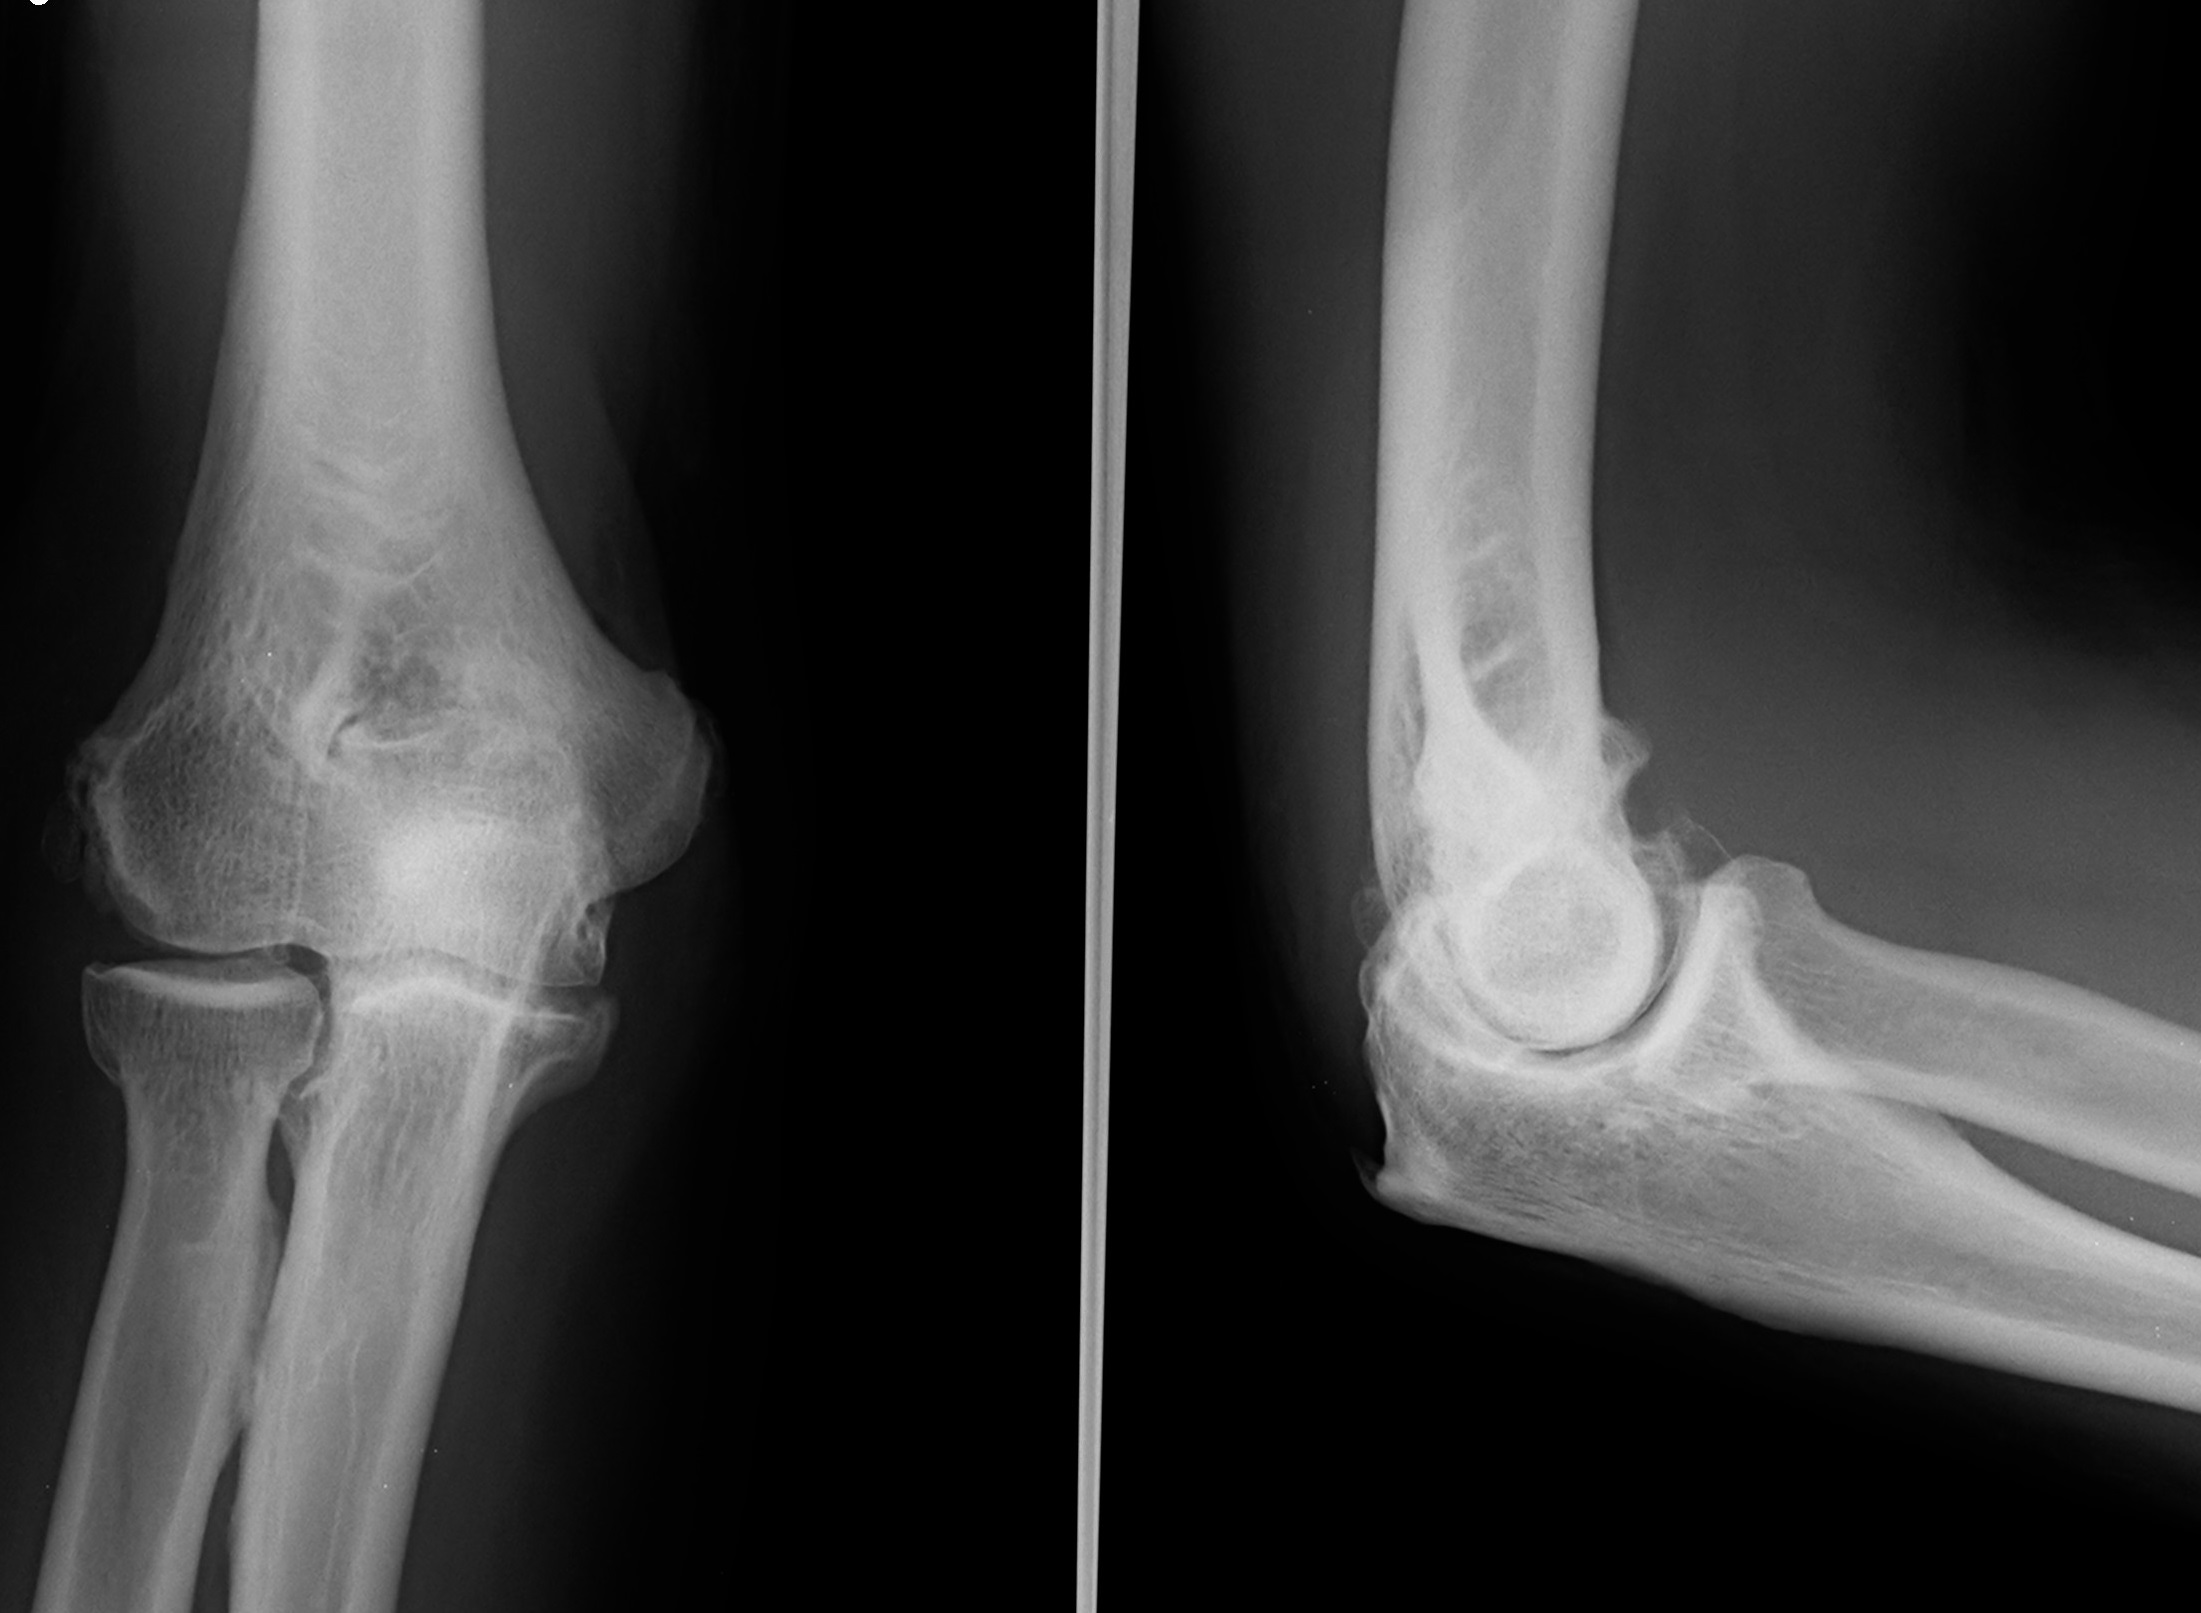

B 断層撮影.橈骨頭関節面1/3の骨折. a 肘後方脱臼骨折を認める. c 断層撮影.腕尺関節の肘亜脱臼と鈎状突起骨折 を認めた. 図-7 症例2 受傷時X線 ab 整復位は保たれ,鉤状突起の形状も良好である. 図-8 症例2 術後6週のX線脱臼した患者は仰向けで寝るか、 または体がしっかり安定する所に座ります。 肘関節の屈曲角度は脱臼した形のままで 手首と肘部を把持して 前腕の末梢方向に ゆっくり牽引を強めていき 牽引を持続しながら 肘関節を曲げます。脱臼していない肘関節では、肘関節の屈曲の度合に関わりなく、橈骨頭と上腕骨小頭は全方向のX線像上で同一線上に並びます。 外傷の際にはfat pad signが認められることがあります。

肘関節脱臼や肘関節内側側副靭帯損傷(MCL損傷)は日常診療でよくみかける外傷です 肘関節の解剖ですが内側側副靭帯は、前斜走靭帯(anterior oblique ligament;六訂版 家庭医学大全科 肘関節脱臼の用語解説 どんな外傷か 肘関節は、上腕骨(じょうわんこつ)と2本の前腕骨(ぜんわんこつ)(橈骨(とうこつ)・尺骨(しゃっこつ))とで形成される関節で、上腕骨内側の滑車(かっしゃ)という部分と、尺骨の肘頭とカギ型の部分とが強くからみ合って、曲げ伸ば腕尺関節の脱臼骨折をさしている 肘関節脱臼 骨折はその治療において, 合併骨折時に関節内 骨折の処置や軟部組織の処置ばかりでなく, 後 療法や合併する神経麻痺の予後など多くの問題 をふくんでいる 今回, 我々は昭和63年4月 よ り約6年 間に腕尺関節の